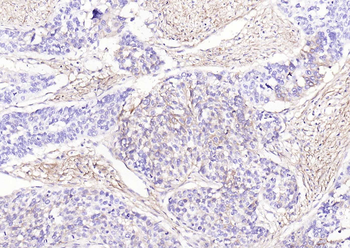

IHC staining of FFPE human prostate carcinoma with CD73 antibody (clone NT5E/2545). HIER: boil tissue sections in pH9 10mM Tris with 1mM EDTA for 10-20 min and allow to cool before testing.